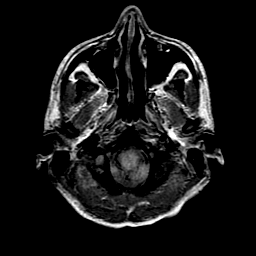

Sarcoma, MR Study #1 mr-pd -- Slice #1

[Home][Help][Clinical] Slice 1